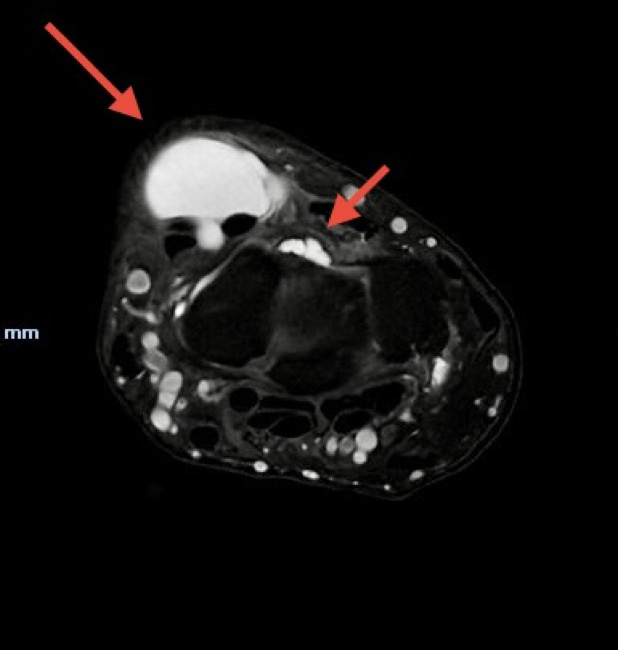

Normalmente são necessários alguns raios-X e uma ressonância magnética para melhor caracterização e exclusão de patologia associada dentro do punho.

Imagem de ressonância magnética demonstrando volumoso quisto sinovial dorsal, insinuando-se junto ao ligamento escafo-lunar